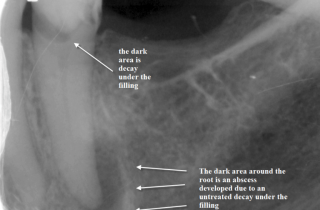

Our teeth consist of enamel, dentine, cementum and pulp tissue. Enamel: is the outer layer that is visible above the …